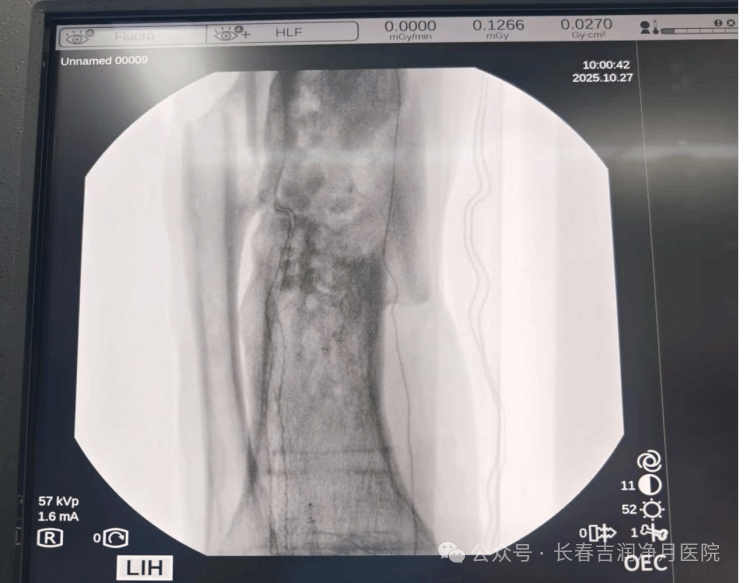

2025年10月,张先生入住我院接受决定性治疗。于铁成主任团队经过充分准备,为患者实施第二阶段手术。术中通过精准操作,完整取出抗生素链珠,彻底清创后植入抗生素硫酸钙骨粉。手术过程顺利,耗时短,创伤小。

术后随访显示,骨折愈合良好,感染指标完全正常,患肢已恢复正常功能。

(2025年10月,第二次手术术中胫腓骨正侧位)

(术后复查 右胫腓骨正侧位)